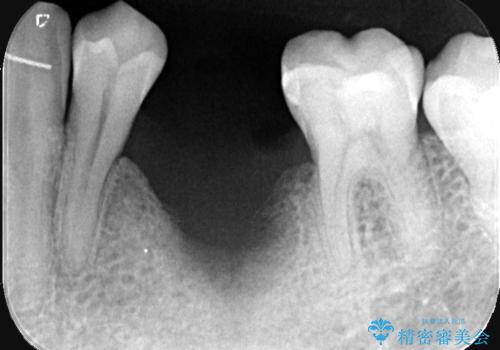

- 20年振りの来院で下顎左右5番にインプラント入れていた患者様です。

右下5番のインプラントは問題ありませんでしたが、左下5番のインプラントがインストール周囲炎に罹患している状態でした。

インプラントを抜去後、再びインプラントで治療を行いました。

インプラントは虫歯にはなりませんが、しっかりケアをしないと歯周病にはなってしまいます。

歯周病は歯の病気ではなく、骨の病気なので歯やインプラントは骨に支えられているため進行すると揺れてきてしまいます。

なので、衛生士による定期的なクリーニングはとても大事です。